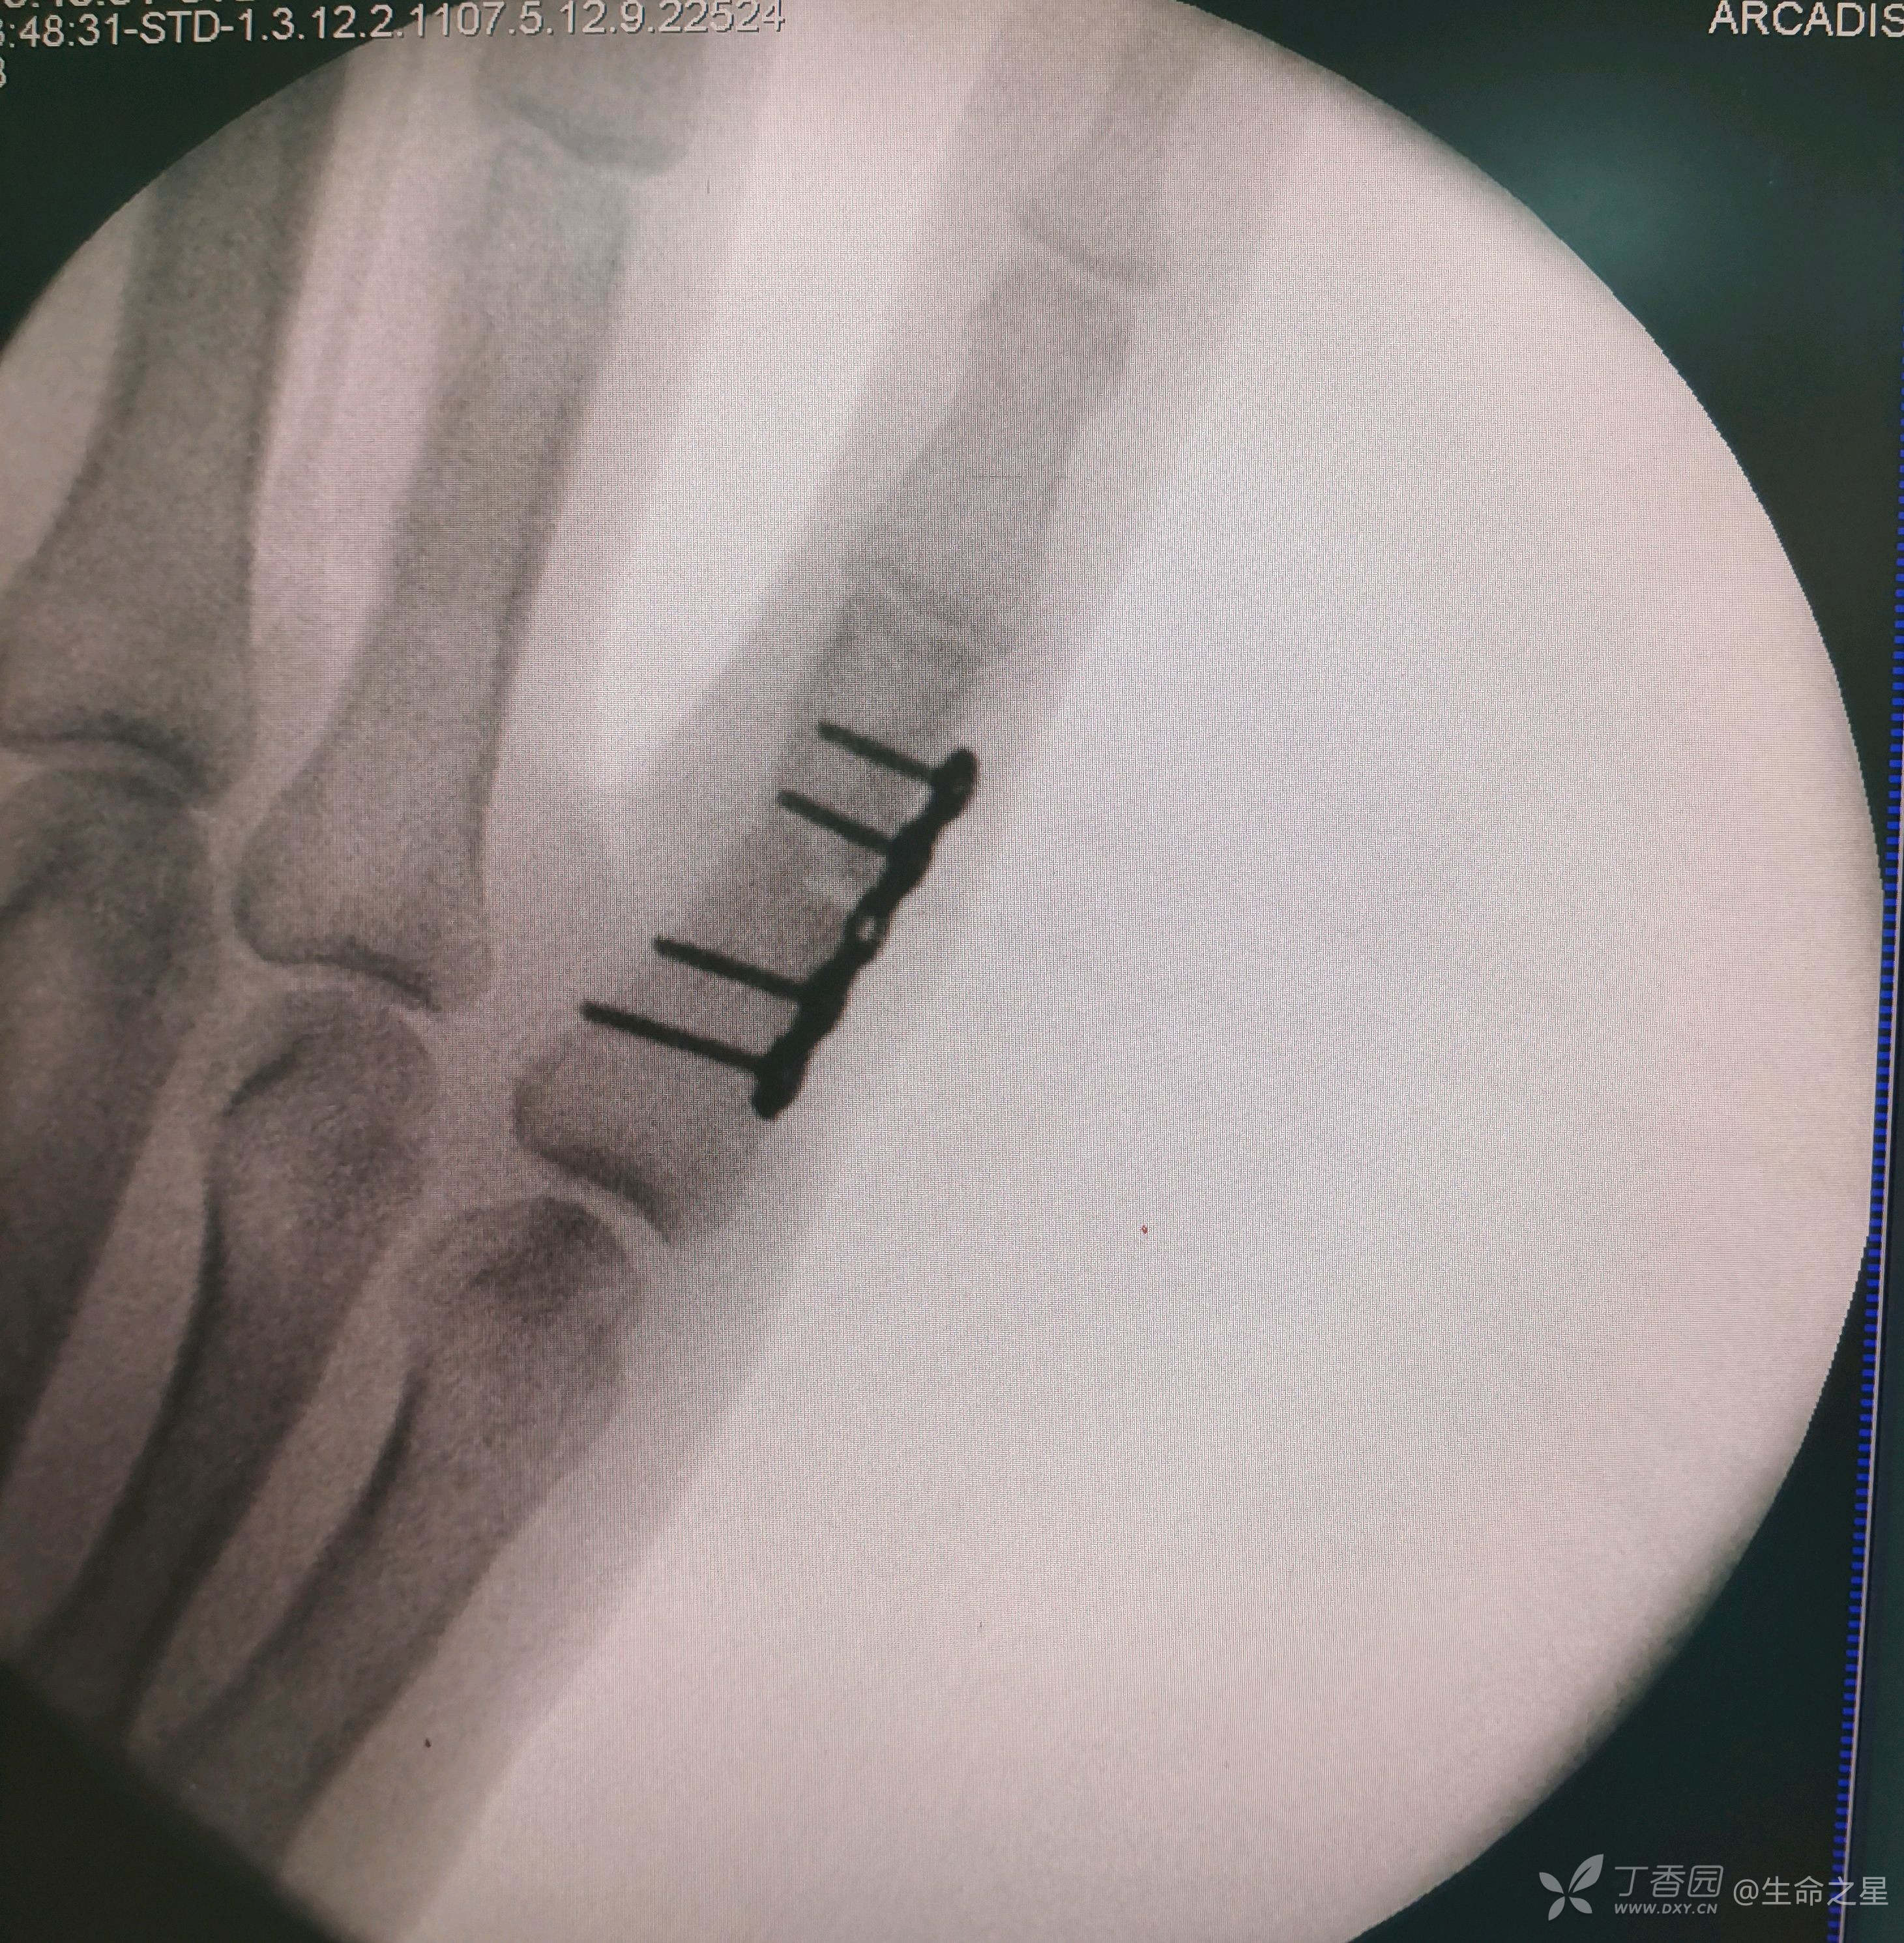

手术给予行切开复位内固定

手术耗时40分钟。

个人体会,手部及足部骨折,骨质小,操作难度大,要避免反复操作及返工,要一次到位,往往更考验技术

同一天做了股骨髁上和骶髂拉力螺钉,感觉做这手指时紧张出汗了😂